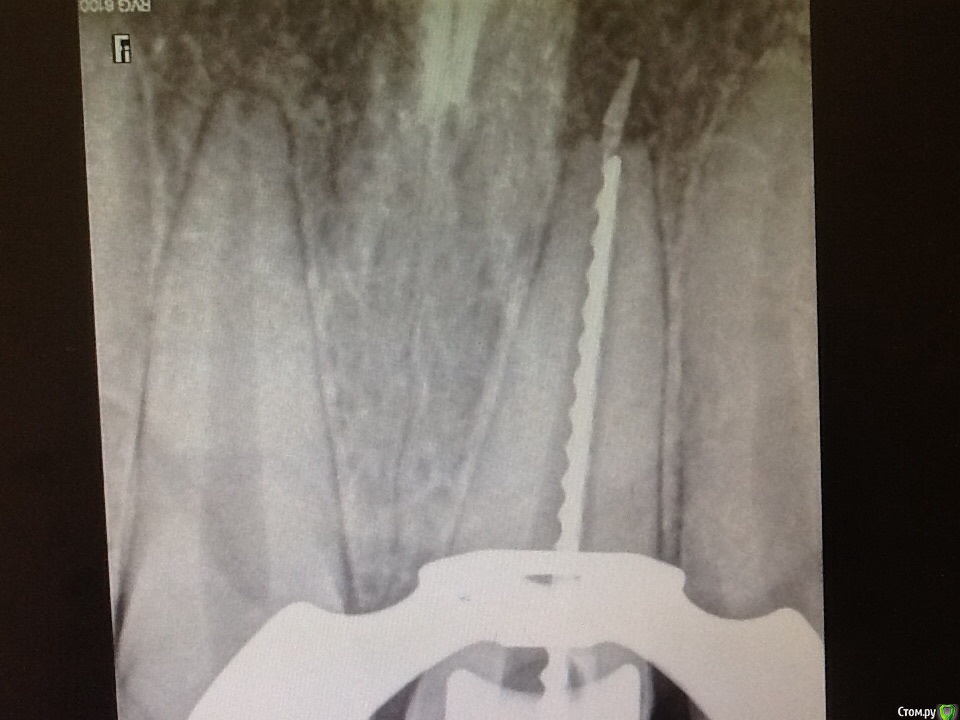

Ico Опубликовано 29 мая, 2015 Поделиться Опубликовано 29 мая, 2015 Расширить до 100 - 130,попытаться вкрутить в него 10 или 15 хедструм и удить.Если не получилось,то в эндошприц набрать гуттасольв или эндосольв но только не масло и создать депо в апексе,толстым машту понагнетать немного,подождать.Берм адсорбенты апекально сушим)))случалось,что удавалось его растворить.http://imhocloud.com/images/2015/05/29/APOM3097b.jpg Ссылка на комментарий

Л Ю С Я Опубликовано 29 мая, 2015 Автор Поделиться Опубликовано 29 мая, 2015 (изменено) Спасибо всем отозвавшемся. Хирургию пока исключаем по причине во - первых наличия у пациента тромбоцитопинии после перенесенного гепатита, можно , конечно, но в стационар я его из за куска гутты не отправлю. Во- вторых, я знаю как наши хирурги это делают и там будут все последствия, которые упоминал Ico, Расширить до 100 - 130,попытаться вкрутить в него 10 или 15 хедструм и удить.Если не получилось,то в эндошприц набрать гуттасольв или эндосольв но только не масло и создать депо в апексе,толстым машту понагнетать немного,подождать.Берм адсорбенты апекально сушим)))случалось,что удавалось его растворить. До 130 расширять??? Лучше уж наверно эндосольфа налить. Кстати, сколько ждать?Если не получиться так оставлю. Изменено 29 мая, 2015 пользователем Л Ю С Я Ссылка на комментарий

Ico Опубликовано 29 мая, 2015 Поделиться Опубликовано 29 мая, 2015 (изменено) Спасибо всем отозвавшемся. Хирургию пока исключаем по причине во - первых наличия у пациента тромбоцитопинии после перенесенного гепатита, можно , конечно, но в стационар я его из за куска гутты не отправлю. Во- вторых, я знаю как наши хирурги это делают и там будут все последствия, которые упоминал Ico,До 130 расширять??? Лучше уж наверно эндосольфа налить. Кстати, сколько ждать?Если не получиться так оставлю.Если видите его в скоп,то можно и не расширять.Нужно получить белую стружку в апексе от этого и отталкиваться,все равно там МТА будет или IRM.Помните постил?http://imhocloud.com/images/2015/05/29/2014-01-27-70056b4e.md.jpg тоже резорбция была,кофом тогда не работал,но в итоге пока жив. Изменено 29 мая, 2015 пользователем Ico Ссылка на комментарий

Ico Опубликовано 29 мая, 2015 Поделиться Опубликовано 29 мая, 2015 (изменено) Типа удочки с крючком? да,2мм под 90 градусов,но апекс должен быть 80-100.Если брать меньшие номера,кончик отвалиться Изменено 29 мая, 2015 пользователем Ico Ссылка на комментарий